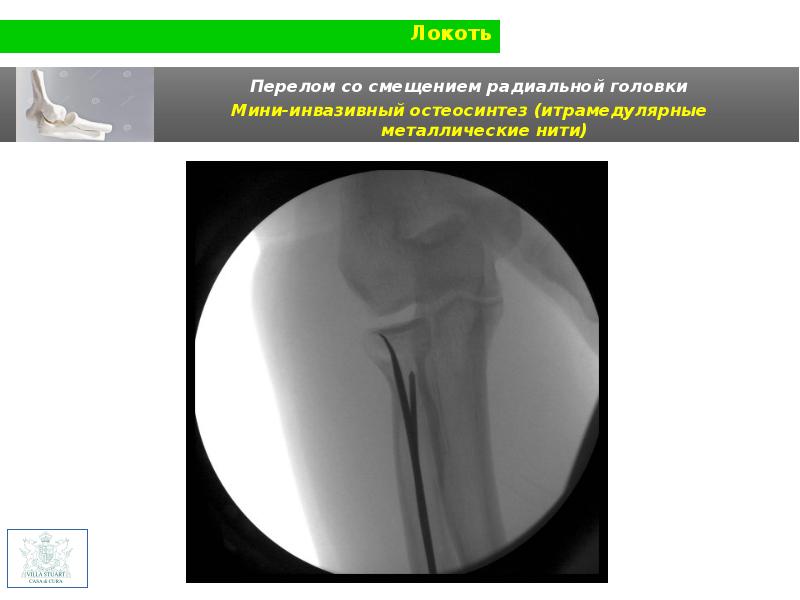

Радиальные головки